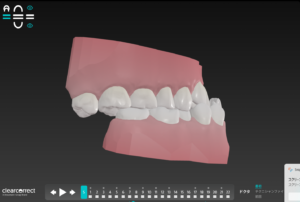

受け口が完全に

クリアコレクトで治るか?の判断は

下の前歯と上の前歯が

くっついているかが目安

今回は残念ながら

下の前歯と上の前歯に

5ミリのスキマがあったので

本来なら

下アゴを1センチ位切断して

短くするオペケース

しかし このオペは保険適応ではあるが

かなり大変なオペで

そうせい が治り

上下の前歯が くっつく なら大丈夫

という事でクリアコレクトで矯正開始

この歯並びが治る原理は

受け口🟰Ⅲ級ゴムで

上の歯列は前に

下の歯列は後ろに けんいん

そうせい🟰歯と歯の間を少し削り

スキマを作って歯をキレイに整列